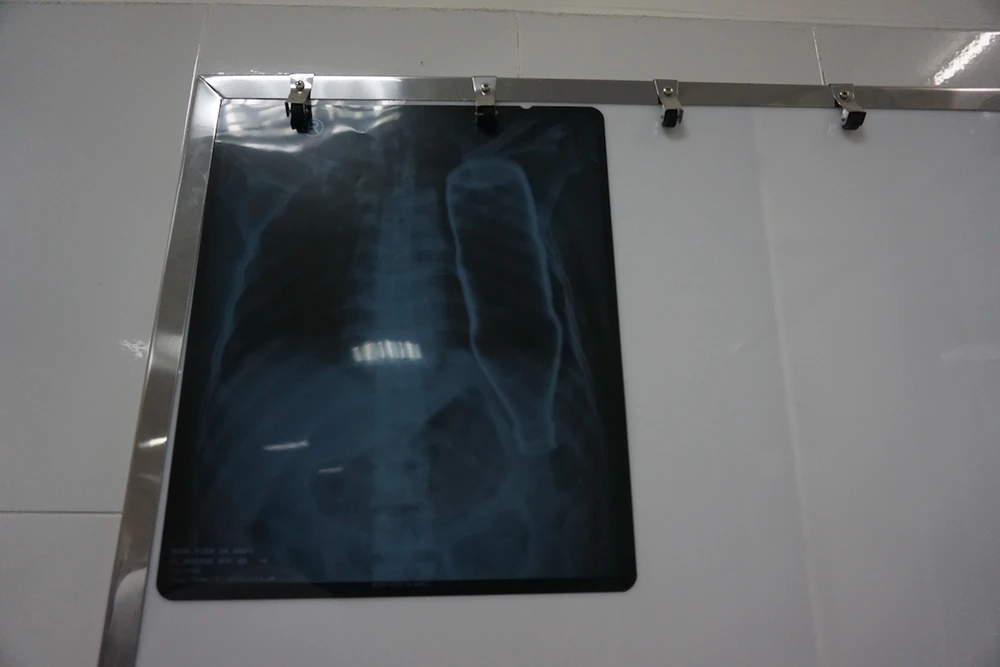

Sau khi tiếp nhận bệnh nhân, BV đã tiến hành chụp X-quang và CT, các bác sĩ ngỡ ngàng khi thấy một vỏ chai thủy tinh còn nguyên vẹn trong lồng ngực bệnh nhân B.

Hiện ông B. đã qua cơn nguy kịch và đang được điều trị tích cực tại BV Đà Nẵng. Ảnh: KIỀU VŨ